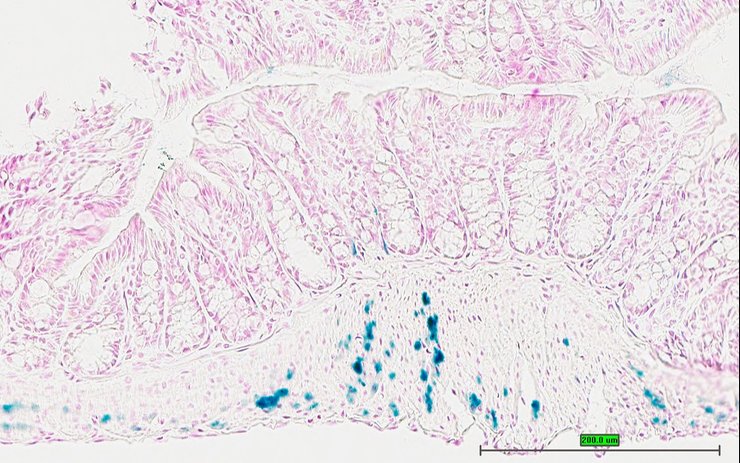

TS28: ileum Present UC Davis_1875947

TS28: ileum Present UC Davis_1875963

Specimen UC Davis_1875964: postnatal adult; Ppbptm1.1(KOMP)Vlcg/Ppbp+ (more )

Structure Level Pattern Image Note

TS28: ileum Present UC Davis_1875964